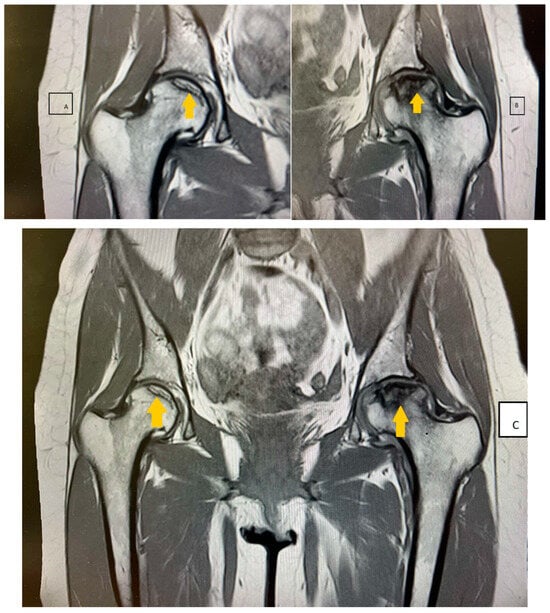

The patient was treated with nadroparin calcium (0.6 mL 2 times a day subcutaneously for 12 days) followed by oral vitamin K antagonist acenocumarol (4 mg) in doses adjusted according to the PT and INR values, metamizole sodium (500 mg) or pitofenone hydrochloride (5 mg) or fenpiverinium bromide (1 tablet of 0.1 mg 3 times a day), and bioflavonoid vasoprotector diosmin (1 tablet of 1000 mg a day). Acenocoumarol was received for 2 months on a regimen and then discontinued again because of massive menstrual bleeding. Four months after the viral infection, the patient started to experience increased pain in her hands, knees, hips, and inguinal region. She also experienced morning stiffness that lasted for about an hour. The non-steroidal anti-inflammatory drugs the patient was taking had no effect. The motor deficit she had gradually progressed to the point of her being unable to move without crutches. A rheumatologist examined the patient and ordered an antinuclear antibody (ANA) test to rule out a systemic disorder. The ANA panel included tests for perinuclear anti-neutrophil cytoplasmic antibodies (p-ANCA), antineutrophil cytoplasmic antibodies (c-ANCA), anti-cardiolipin antibodies IgG, IgM (ACL-IgG, IgM), anti-phospholipid antibodies IgG, IgM (APL-IgG, IgM), anti-beta-2-glycoprotein I IgG, IgM, immunoglobulins IgG, IgA, IgM, and IgE, and complement components C3 and C4. These tests all came back within reference ranges, ruling out rheumatological disease, and the patient was referred to an orthopedist, who recommended a nuclear magnetic resonance examination. The imaging study found a focus of altered structure in the right hip in the pattern of initial avascular changes (Figure 5A). The femoral head of the left joint had deformed convexity and structure, with pronounced medullary edema of the neck and metaphysis, and an area of avascular necrosis measuring 2.24 cm2 (Figure 5B). The femoral head was ultimately determined to have bilateral avascular necrosis (Figure 5C).

Figure 5.

(A) The imaging study revealing focus of altered structure in the right hip in the pattern of initial avascular changes. (B)The femoral head of the left joint has deformed convexity and structure, with pronounced medullary edema of the neck and metaphysis, and an area of avascular necrosis measuring 2.24 cm2. (C) The femoral head was ultimately determined to have bilateral avascular necrosis.